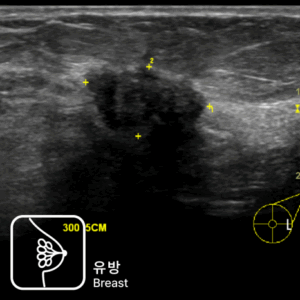

가스 차는 증상과 경미한 혈변으로 발견된 직장암 사례설사와 혈변, 항문 통증으로 내원했다가 직장암을 진단받은 40대 남성 사례심한 변비로 내원하여 상행결장암을 진단받은 80대 남성 사례속쓰림으로 내원했다가 복부초음파로 조기 담낭암을 발견한 사례명치 통증과 소화불량으로 내원했다가 췌장암 3기가 진단된 사례무증상 검진 중 갑상선초음파로 발견된 조기 갑상선 유두암 사례유방 통증으로 내원했다가 유방초음파로 조기 진단된 침윤성 유방암 사례명치 통증으로 내원했다가 진행성 위암을 발견한 60대 여성 사례속쓰림으로 내원했다가 signet ring cell type 위암을 조기 발견한 60대 여성 사례소화불량으로 내원했다가 작은 조기 위선암을 발견한 50대 여성 사례변비로 내원했다가 침윤성 궤양 형태의 위암을 발견한 70대 여성 사례소화불량으로 내원했다가 진행성 위암을 발견한 60대 여성 사례경미한 속쓰림으로 방문했다가 조기 위선암을 발견한 60대 여성 사례가스 차는 증상과 경미한 혈변으로 발견된 직장암 사례설사와 혈변, 항문 통증으로 내원했다가 직장암을 진단받은 40대 남성 사례심한 변비로 내원하여 상행결장암을 진단받은 80대 남성 사례속쓰림으로 내원했다가 복부초음파로 조기 담낭암을 발견한 사례명치 통증과 소화불량으로 내원했다가 췌장암 3기가 진단된 사례무증상 검진 중 갑상선초음파로 발견된 조기 갑상선 유두암 사례유방 통증으로 내원했다가 유방초음파로 조기 진단된 침윤성 유방암 사례명치 통증으로 내원했다가 진행성 위암을 발견한 60대 여성 사례속쓰림으로 내원했다가 signet ring cell type 위암을 조기 발견한 60대 여성 사례소화불량으로 내원했다가 작은 조기 위선암을 발견한 50대 여성 사례변비로 내원했다가 침윤성 궤양 형태의 위암을 발견한 70대 여성 사례소화불량으로 내원했다가 진행성 위암을 발견한 60대 여성 사례경미한 속쓰림으로 방문했다가 조기 위선암을 발견한 60대 여성 사례

30년 경력 의료진의 판독,

세란의 초음파 클리닉

내과·영상의학과 전문의가

직접 검사부터 판독까지

30년 경력의 영상의학과

의료진이 함께하는 신뢰도 높은 진단

당일 검사, 당일 결과 확인 가능합니다.